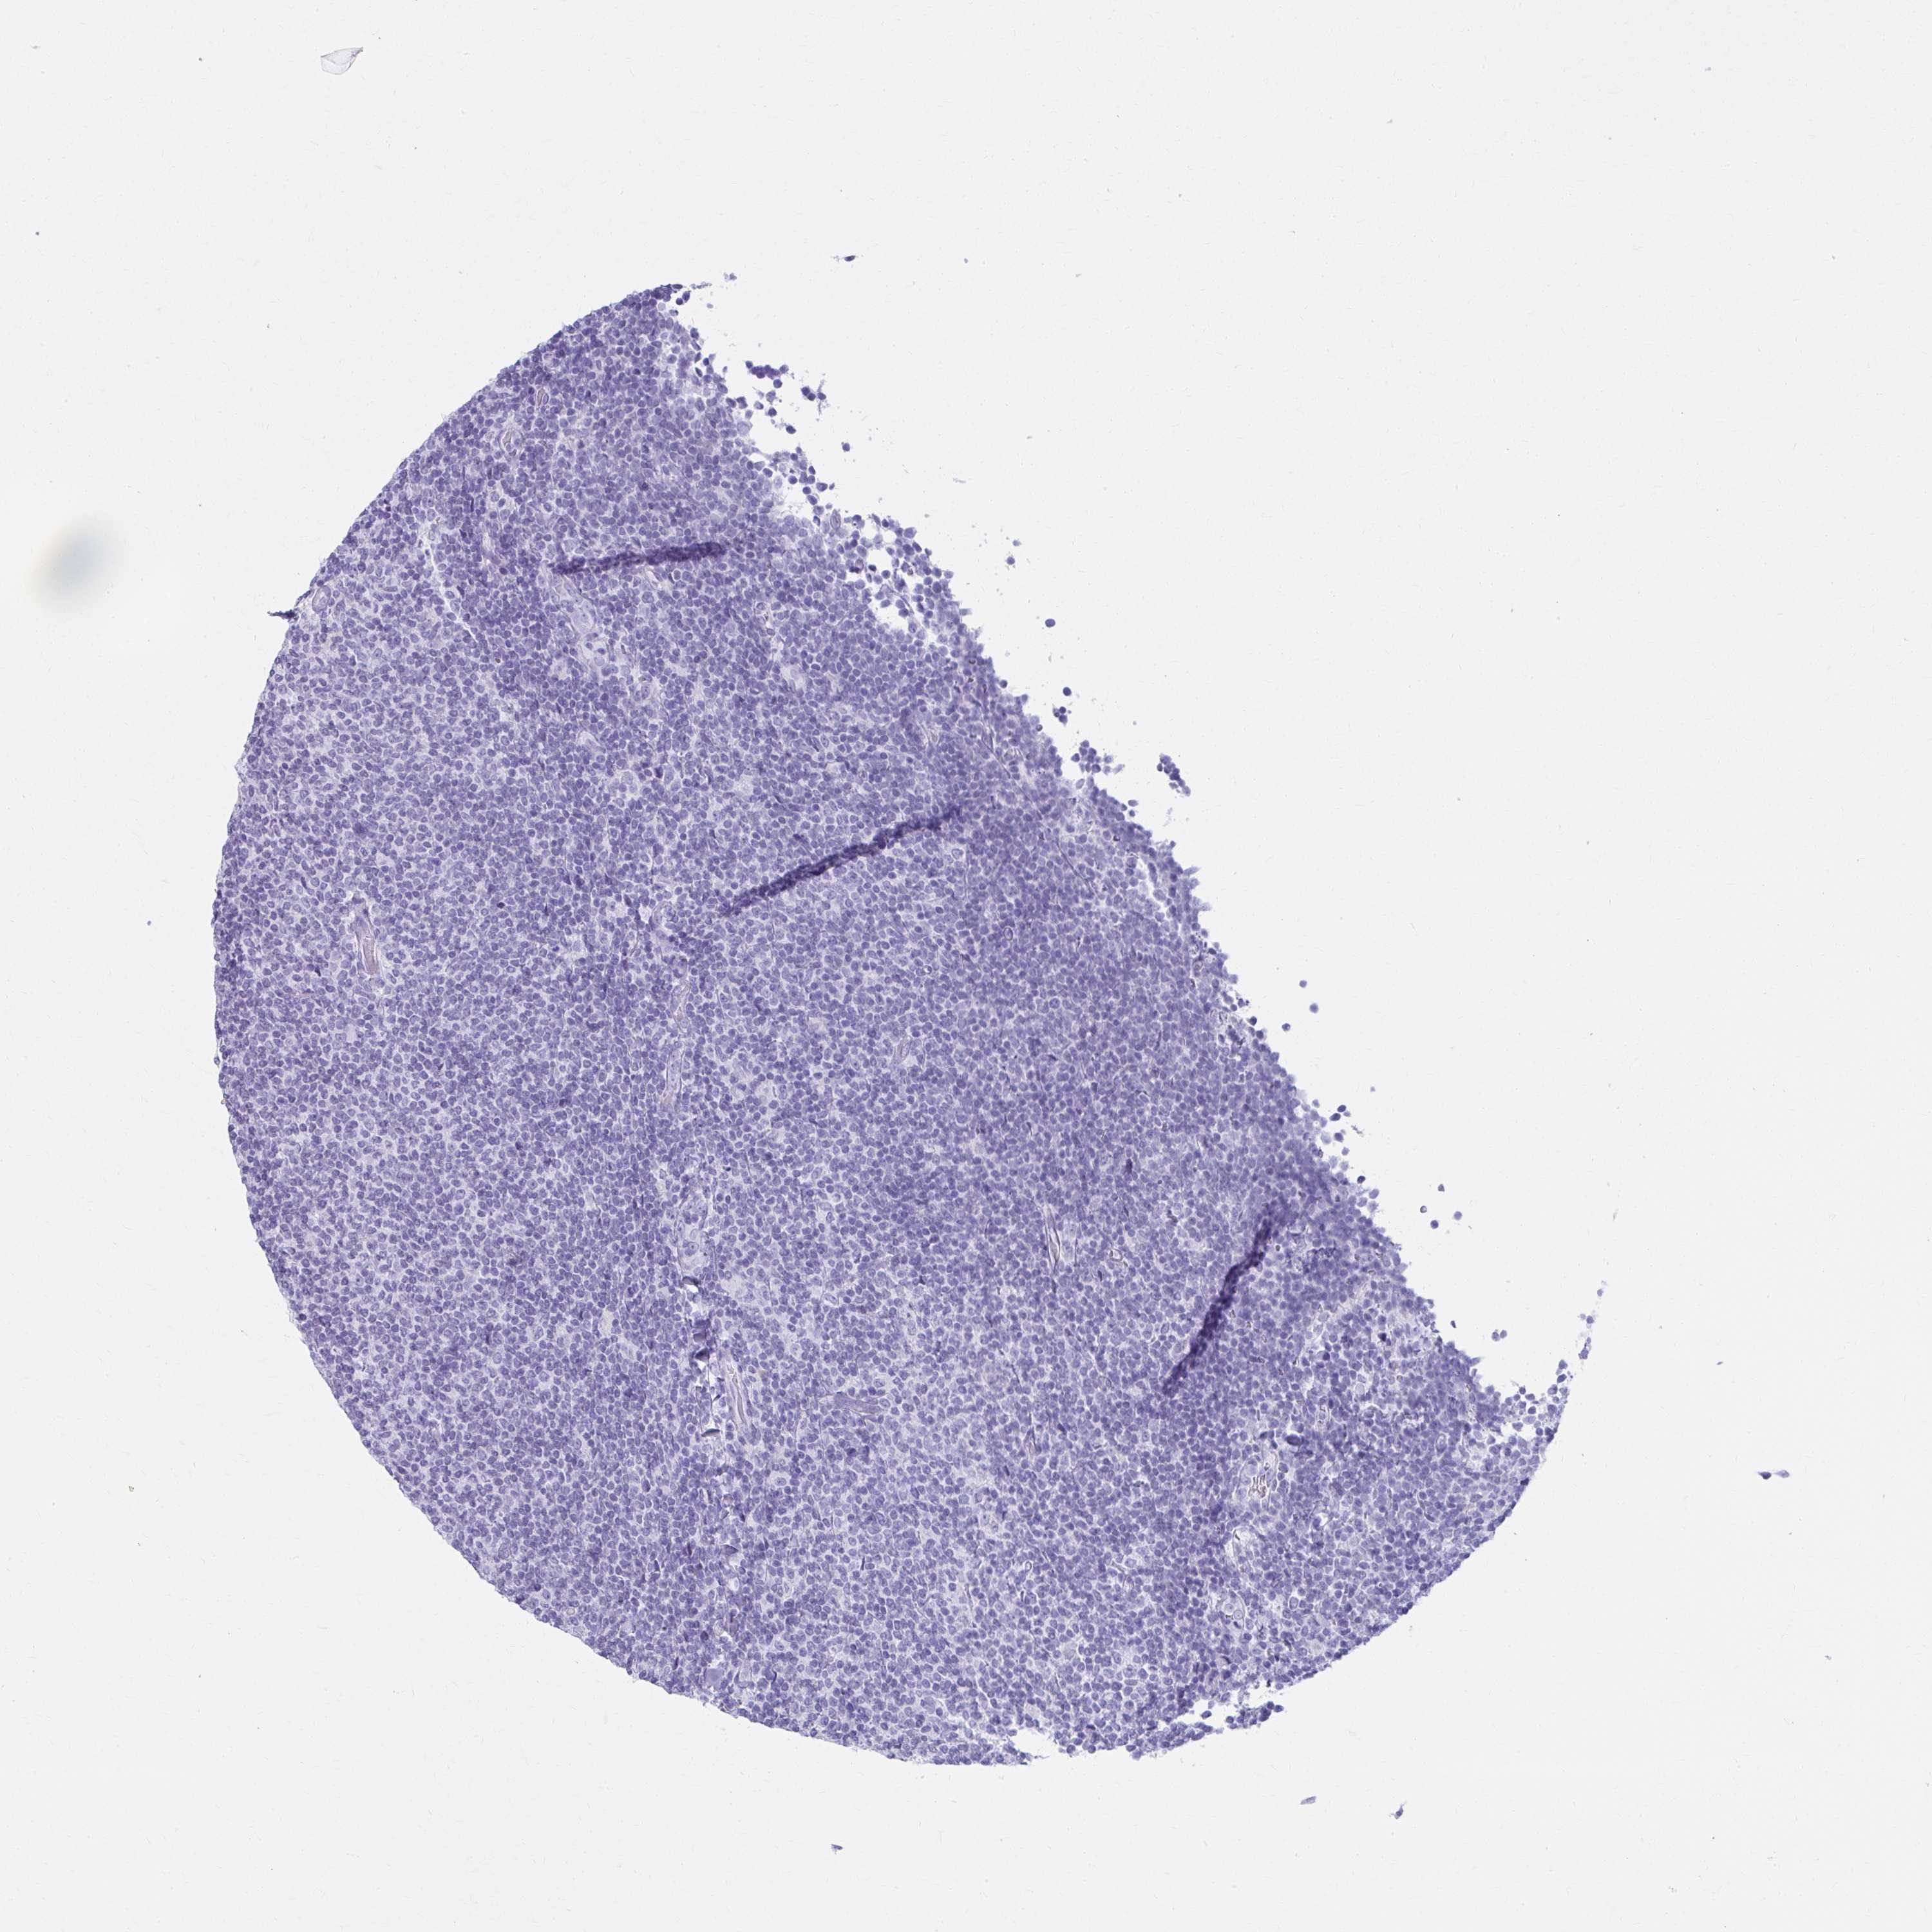

LYMPHOMA - Protein expressioni

A mouse-over function shows sample information and annotation data. Click on an image to view it in a full screen mode. Samples can be filtered based on level of antibody staining by selecting one or several of the following categories: high, medium, low and not detected. The assay and annotation is described here.

Antibody staining in the annotated cell types in the current human tissue is reported as not detected, low, medium, or high, based on conventional immunohistochemistry profiling in selected tissues. This score is based on the combination of the staining intensity and fraction of stained cells.

Each image is clickable and will lead to virtual microscopy that enables deeper exploration of all samples and also displays staining intensity scores, fraction scores and subcellular localization as well as patient and tissue information for each sample.

Antibody HPA045400

Antibody HPA052649

Staining

High

Medium

Low

Not detected

Malignant lymphoma, non-Hodgkin's type, Low grade

Malignant lymphoma, non-Hodgkin's type, High grade

Hodgkin's disease, NOS